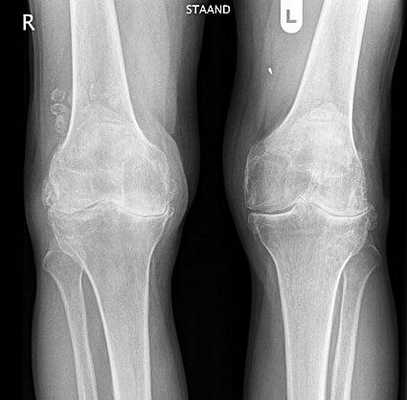

Гонартроз обоих коленных суставов.